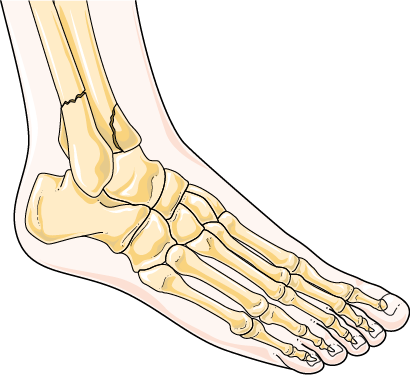

Traumáticas

Causadas por golpes ou feridas. Exemplos: fractura, queimadura, contusión, fisura, intoxicacións...

Fractura de ósos no nocello

Smart . Fractura (CC BY-SA)

7. Traumáticas

Causadas por golpes ou feridas.

Exemplos: Fracturas, queimaduras, contusións, fisuras, intoxicacións.